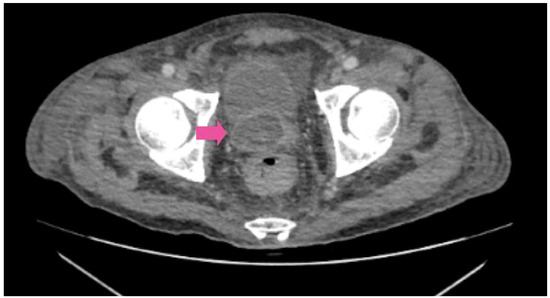

A lung computed tomography (CT) scan revealed a miliary pattern (Figure 1). M. tuberculosis was confirmed via real-time polymerase chain reaction (RT-PCR) GeneXpert® and Mycobacterial Growth Indicator Tube (MGIT) culture testing on sputum. Abdominal CT scans revealed an 18-cc abscess affecting the prostate and the right seminal vesicle (Figure 2). Urine culture and RTPCR for Chlamydia trachomatis and Neisseria gonorrhoeae were negative. Transurethral drainage of the prostatic abscess was performed, and RTPCR of the sample identified M. tuberculosis confirming the diagnosis of a tuberculosis prostate abscess. Susceptibility of M. tuberculosis to rifampin by RT-PCR was documented.

Figure 2. Axial pelvis CT-scan: Prostatic abscess of 18 cc, with compromise of the right seminal vesicle.